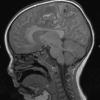

HSV-I Encephalitis (2)